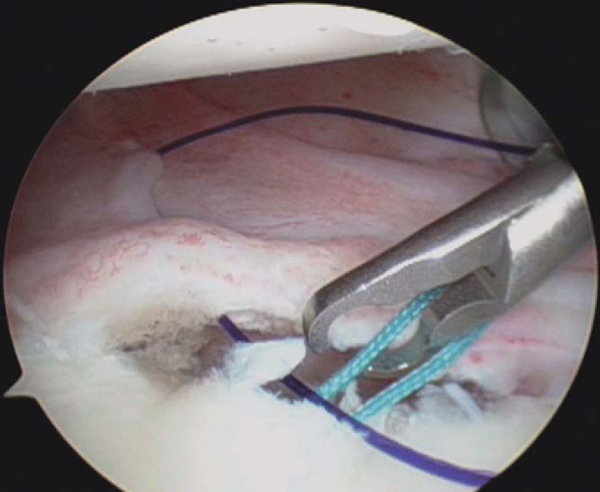

4. Suture Anchor Insertion and Suture Passage

Through the anterosuperior portal, a grasper is used to retrieve the shuttle stitch and pull it out the anterosuperior portal (

Fig. 3-10B

). At this time, upward retraction of this temporary stitch will allow a determination of how much superior shifting of the capsulolabral tissue is possible and, therefore, where the suture anchor should be correctly placed. Excessive tension on this first stitch will increase the likelihood of a knot’s loosening. We prefer the Bio-FASTak suture anchor preloaded with No. 2 FiberWire (Arthrex, Inc., Naples, Fla). The primary advantage of this suture anchor is that the implant can be placed without the use of a drill. The hole is initiated with a sharp trocar and then tapped by hand. The suture anchor is passed through the anteroinferior portal and placed 1 to 2 mm onto the articular margin (

Fig. 3-11

). After anchor insertion, the suture tails must be separated and cleared of any twists. A knot pusher may be placed on one strand of the suture and passed down the cannula. While the knot pusher is inserted, the more inferior or anterior limb is identified. This limb is then retrieved through the anterosuperior portal with a ringed grasper (

Fig. 3-12

). It is imperative to clamp or to hold the opposite limb that is exiting the anteroinferior portal to prevent “unloading” of the suture from the anchor.

|

Figure 3-12 |